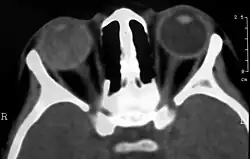

Визуализирующие исследования, такие как ультразвуковое исследование (УЗИ), компьютерная томография (КТ) и магнитно-резонансная томография (МРТ) могут помочь диагностике. На УЗИ, болезнь Коутса выглядит как гиперэхогенная масса в задней части стекловидного тела без задней акустической тени; также наблюдаются кровоизлияния в стекловидное тело и субретинальную область[8][9].

На КТ, гиперплотный шар появляется на фоне обычного стекловидного тела из-за белкового экссудата, который может уничтожить стекловидное тело на поздних стадиях заболевания. Передний край субретинального экссудата усиливается с контрастом. Поскольку сетчатка фиксируется сзади оптического диска, это усиление имеет V-образную конфигурацию[4].